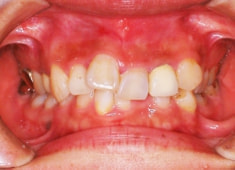

症例紹介

右下7番欠如歯(保存不可能歯につき抜歯)右下8番利用

治療法:フルパッシブブラケット:クリアスナップ

治療前